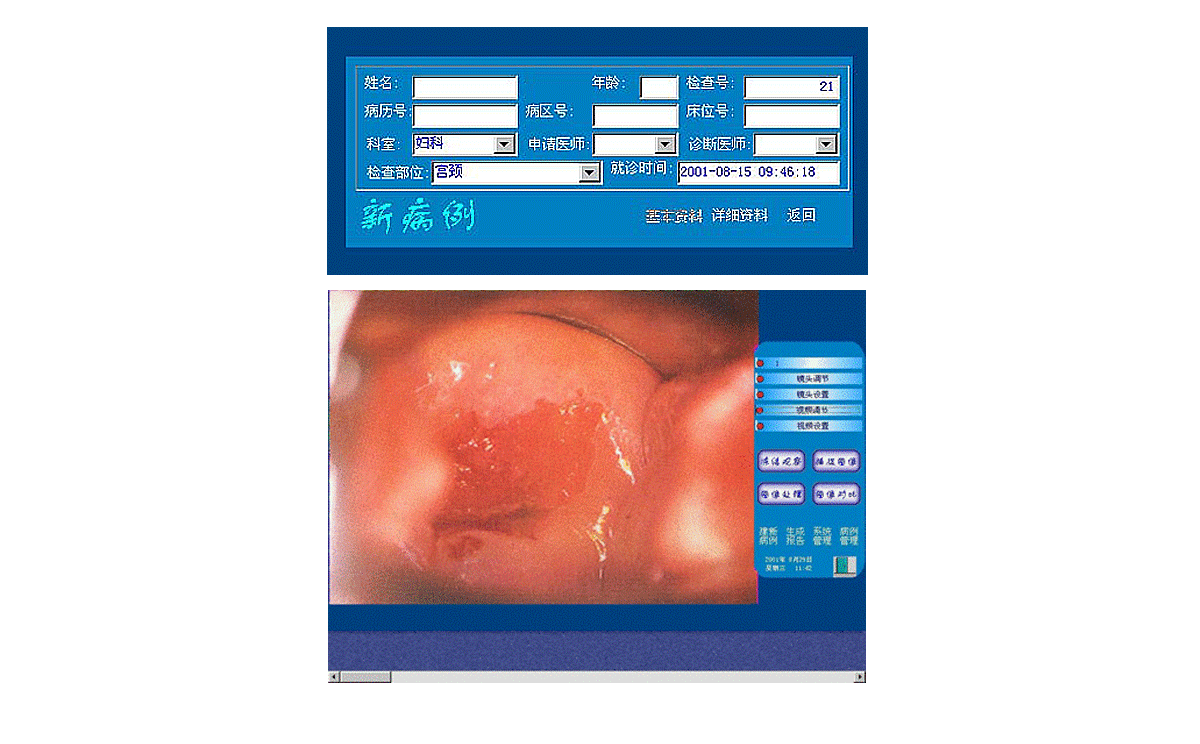

3、打開顯視器電源開關(guān),開啟主機(jī)電源總開關(guān),開啟陰道鏡系統(tǒng),待系統(tǒng)進(jìn)入正常窗口界面后,先創(chuàng)建新病例,通過觀察、采集、生成報(bào)告后,即可完成整個(gè)陰道鏡檢查與診斷操作。

2、用鼠標(biāo)點(diǎn)擊主界面窗口中<建新病例>按鈕后輸入病人的一些資料,再點(diǎn)擊該窗口上的<返回>按鈕,系統(tǒng)進(jìn)入圖像采集窗口界面,這時(shí)圖像采集窗口將顯示陰道鏡所觀察到的動(dòng)態(tài)影像。